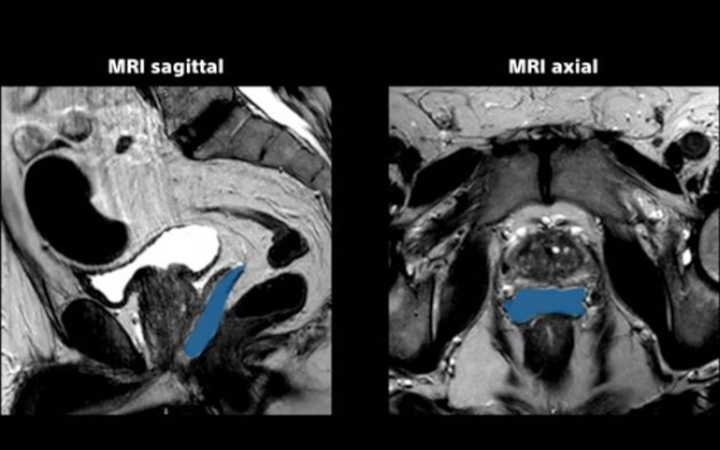

SpaceOAR Hydrogel ist eine resorbierbare, injizierbare Substanz, die bei Prostatakrebspatienten, die sich einer Strahlentherapie unterziehen, einen Abstand zwischen Rektum und Prostata schafft.

Das SpaceOAR Hydrogel dient als vorübergehenden Abstandshalter zwischen Rektum und Prostata. Durch den von SpaceOAR Hydrogel zusätzlich geschaffenen Abstand zwischen Prostata und Rektum wird die an das Rektum abgegebene Strahlendosis reduziert.